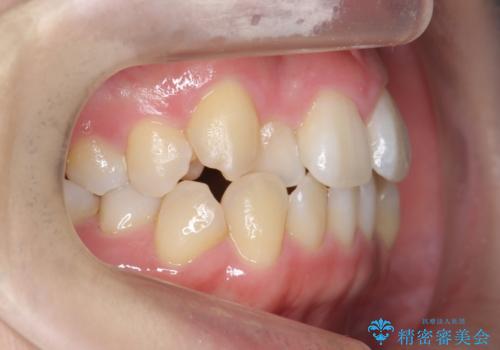

- 20代女性

- 2年3ヶ月

- 前歯のがたつきと正中のずれを主訴に来院。

小臼歯を4本抜歯しています。

歯を抜いたことで、口元が下がって、横顔も理想的なラインになりました。